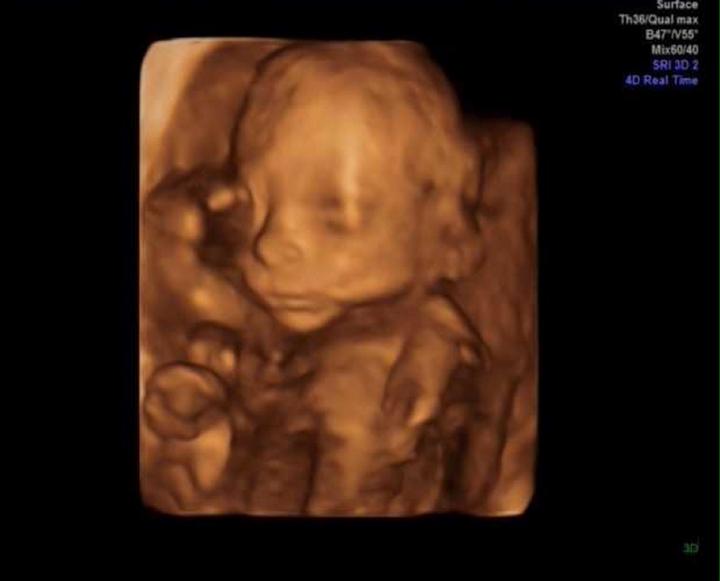

Dneska vám přikládám fotku naší princezny z 3D ultrazvuku. Bylo to krásný, určitě všem doporučuju si tento zážitek dopřát, pokud o něm uvažujete. Zpočátku se nám malá nechtěla ukázat, měla nějaký ultrazvuk těžce na párku. Pupeční šňůru měla ležérně přehozenou přes hlavu, vystrkovala na nás prcinu. Paní doktorka mě pak poslala se trošku projít, jestli se malá neumoudří a neukáže se nám, když se troško rozhýbám. Tak jsem si koupila kávu, sladkou tyčinku, a běhala jsem po schodech nahoru a dolů jak magor. A podařilo se. Pomalu jsem ani nedýchala, jak jsem byla zvědavá, co uvidíme. Na videu pak bylo vidět, jak se malinká pitvoří, hýbe se, vážně super zážitek. Už se na to naše děťátko moc těším, až ji budu držet v náručí, až si k ní přivoním. 🙂